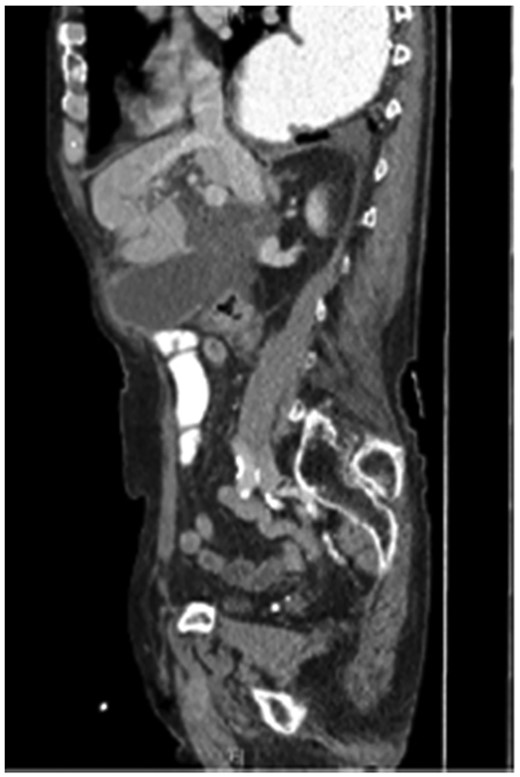

Seventy-six-year-old male with a past medical history of COPD and esophageal cancer status post gastric pull-through procedure 25 years prior, presented to the Emergency Department with a chief complaint of sudden onset epigastric pain that began 24 hours prior while at rest. The pain progressively worsened and radiated to both his right upper quadrant and back with associated chills and nausea/vomiting. He was found to be febrile (38.1C) with a leukocytosis (18.77), hyperbilirubinemia (2.8), transaminitis (418/196) and elevated alkaline phosphatase (168) and lipase (>2250). A CT abdomen/pelvis with IV contrast demonstrated a thickened gallbladder wall, pericholecystic fluid and associated edema of the pancreas consistent with acute cholecystitis and pancreatitis. While the CT showed postoperative changes given his history of esophagectomy with gastric conduit, multiple unique anatomic abnormalities were also noted, including the presence of the gallbladder through a ventral hernia to where it was flush with the skin/subcutaneous tissue of the anterior abdomen (Figs 1 and 2). By hospital day 2, the patient’s lab values were downtrending, consistent with a transient common bile duct stone. Follow-up MRCP confirmed the diagnosis of acute calculous cholecystitis with obstruction of the cystic duct and patency of the common bile and pancreatic ducts. The decision was made to take the patient to the operating room for cholecystectomy with cholangiography. In the operating room, a right subcostal incision was made using electrocautery with a hernia sac encountered directly deep to the subcutaneous tissue. The peritoneum of the hernia was opened and the tip of the gallbladder was immediately encountered. On gross examination, necrosis was noted with evidence of microperforation into the hepatic plate, though no gross contamination was present. The gallbladder was dissected off the hepatic plate, the cystic artery was identified and ligated and stones palpable within the cystic duct were milked retrograde prior to ligation of the cystic duct. The gallbladder was removed and sent for definitive pathologic review. The hernia sac and skin were reapproximated in a multi-layered closure but the fascial edges were not amenable to primary closure secondary to both chronicity and size of the incisional hernia. The patient tolerated the procedure well and was able to discharge home on hospital day 5 (Post-operative day 3). Final pathology was consistent with acute calculous gangrenous cholecystitis. The patient was seen for follow-up 1 month post-operatively and was doing well with no complaints or return of symptoms.

The axial section of the abdomen/pelvis CT scan illustrating our patient’s incisional hernia containing his gallbladder.